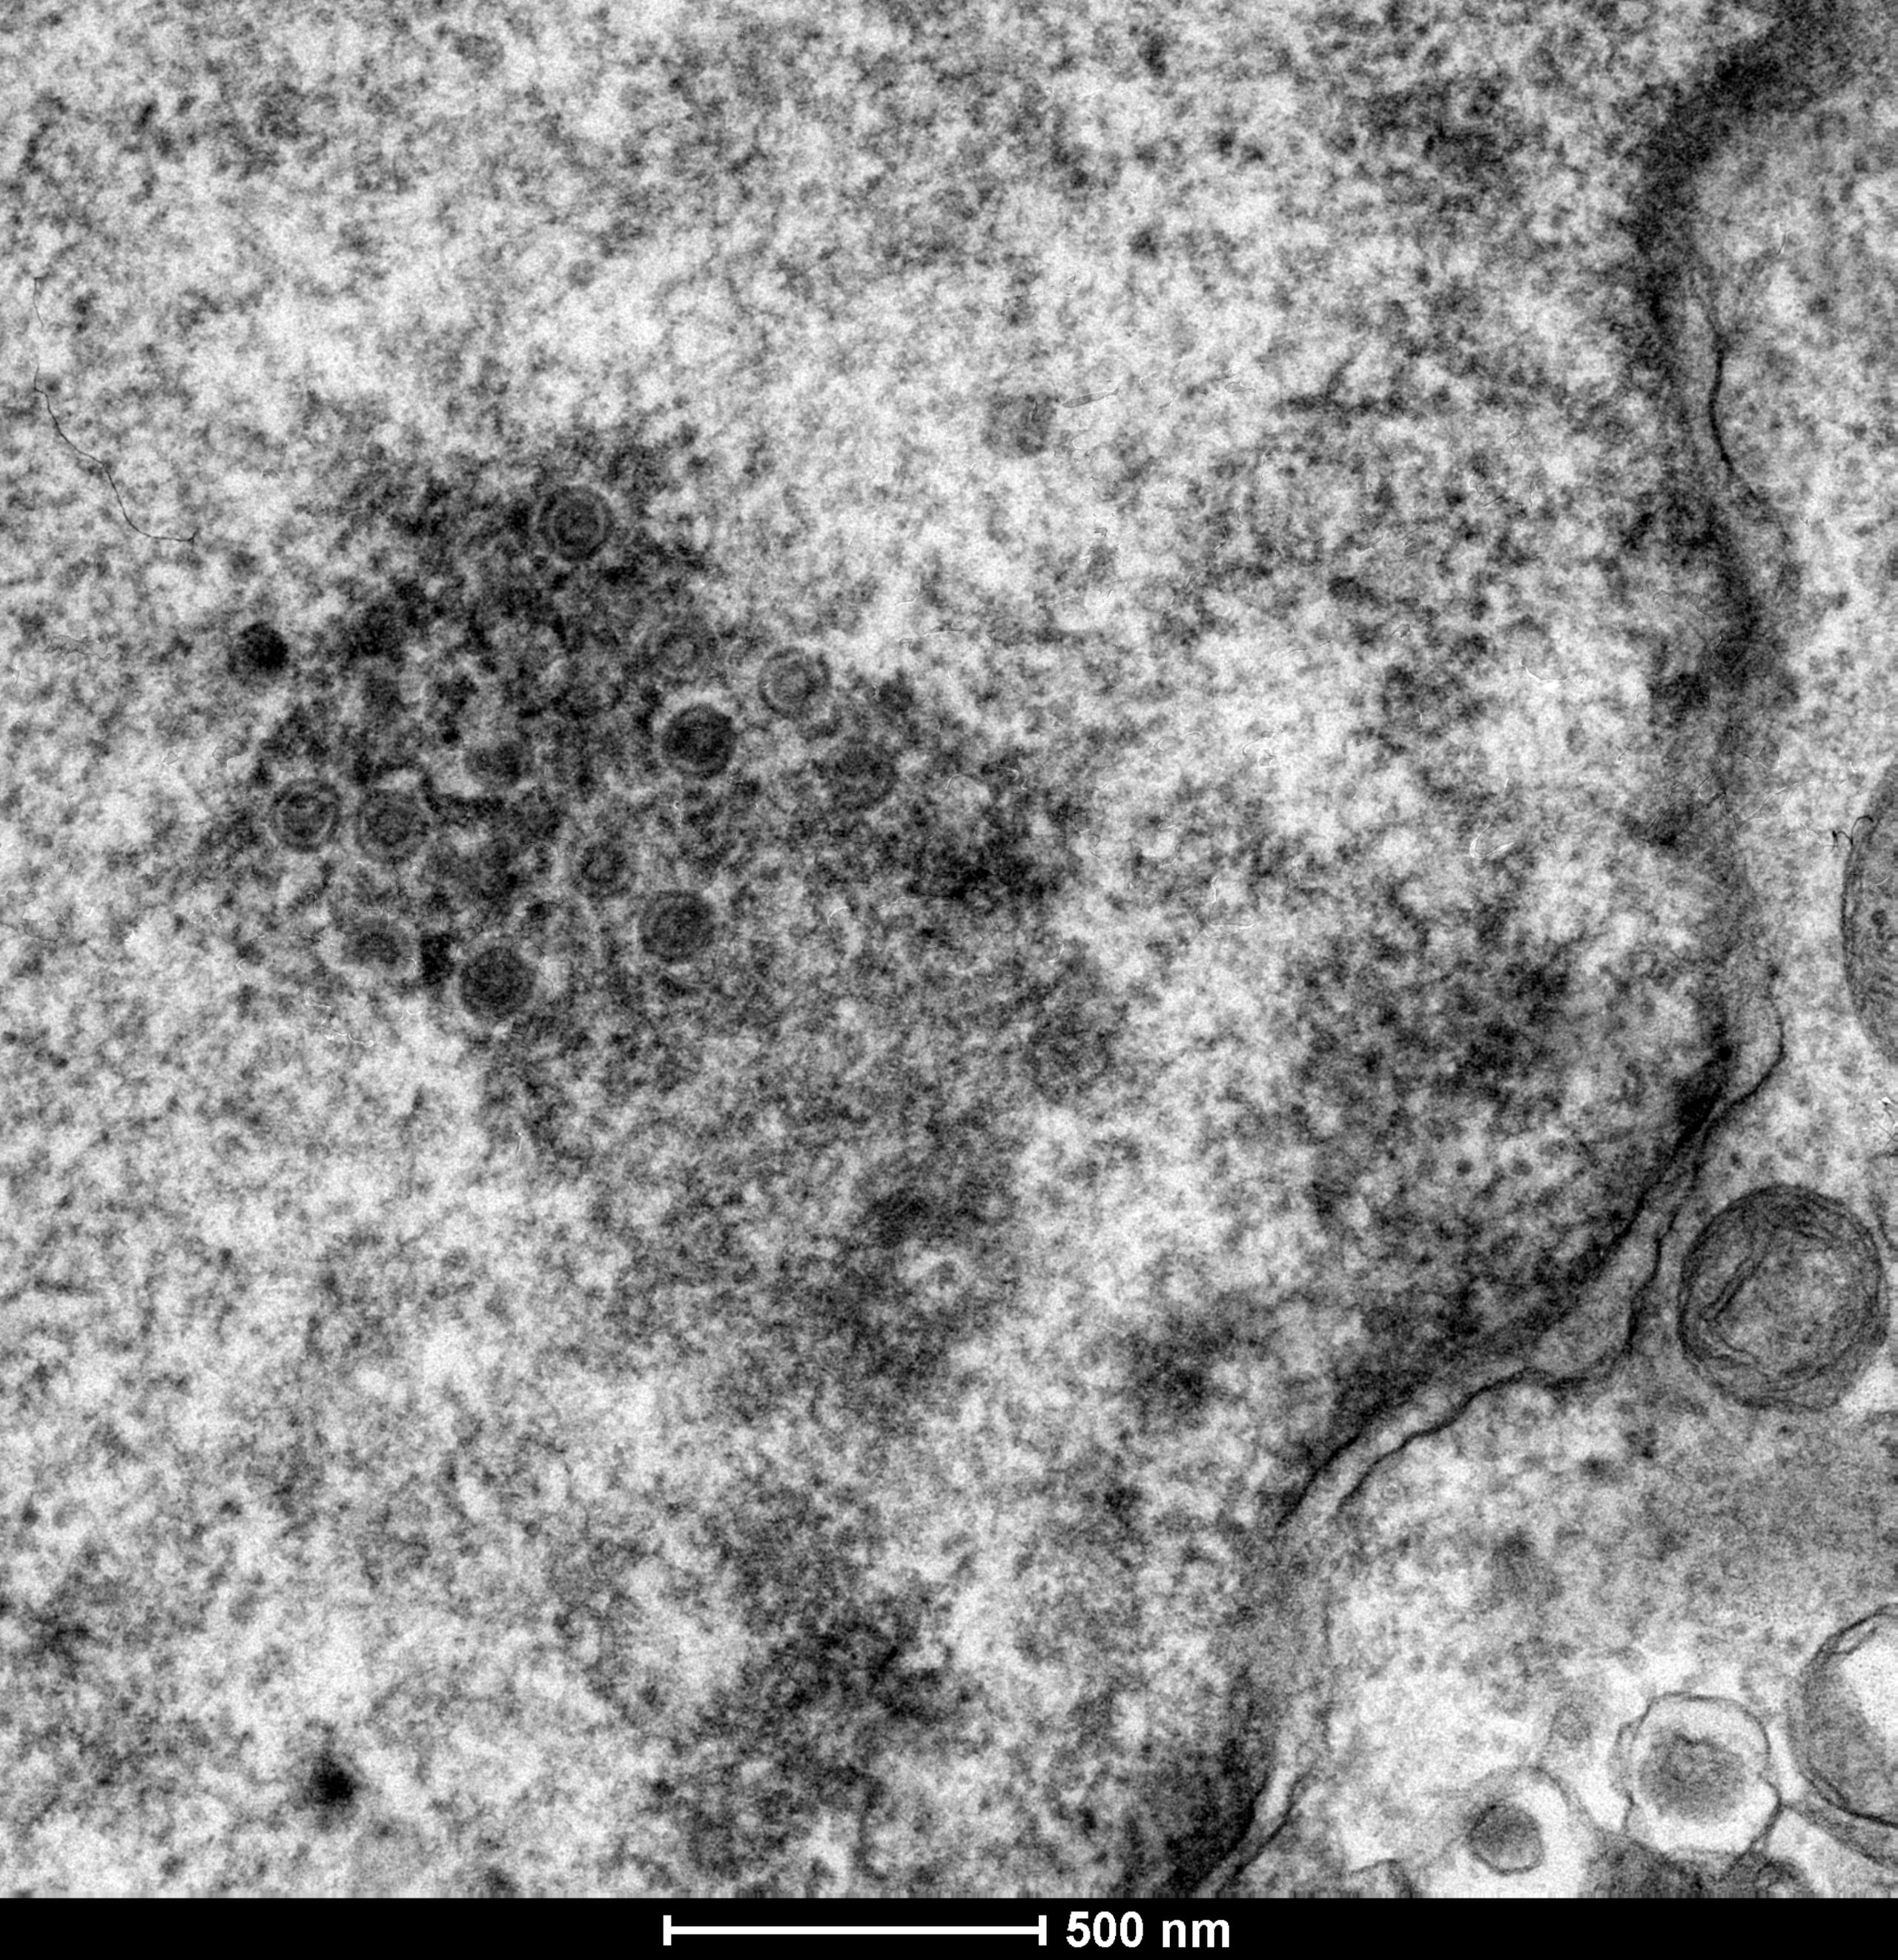

La enfermedad de Marek (MDV), altamente contagiosa y sin cura, es un virus aviar que cada año infecta a miles de pollos no vacunados y cuesta unos mil millones de euros a la industria avícola. Hoy, un estudio ha reconstruido la evolución genética del herpesvirus que lo causa.

La investigación, publicada este jueves en la revista Science, muestra cómo evolucionan los virus para hacerse más virulentos, una información que podría ayudar a desarrollar mejores tratamientos para las infecciones víricas, no solo el MDV.

Además, a partir de las secuencias genéticas antiguas, los investigadores lograron resucitar antiguos procesos biológicos y demostrar que las cepas antiguas eran significativamente más leves que sus homólogas modernas, que son infinitamente más letales.